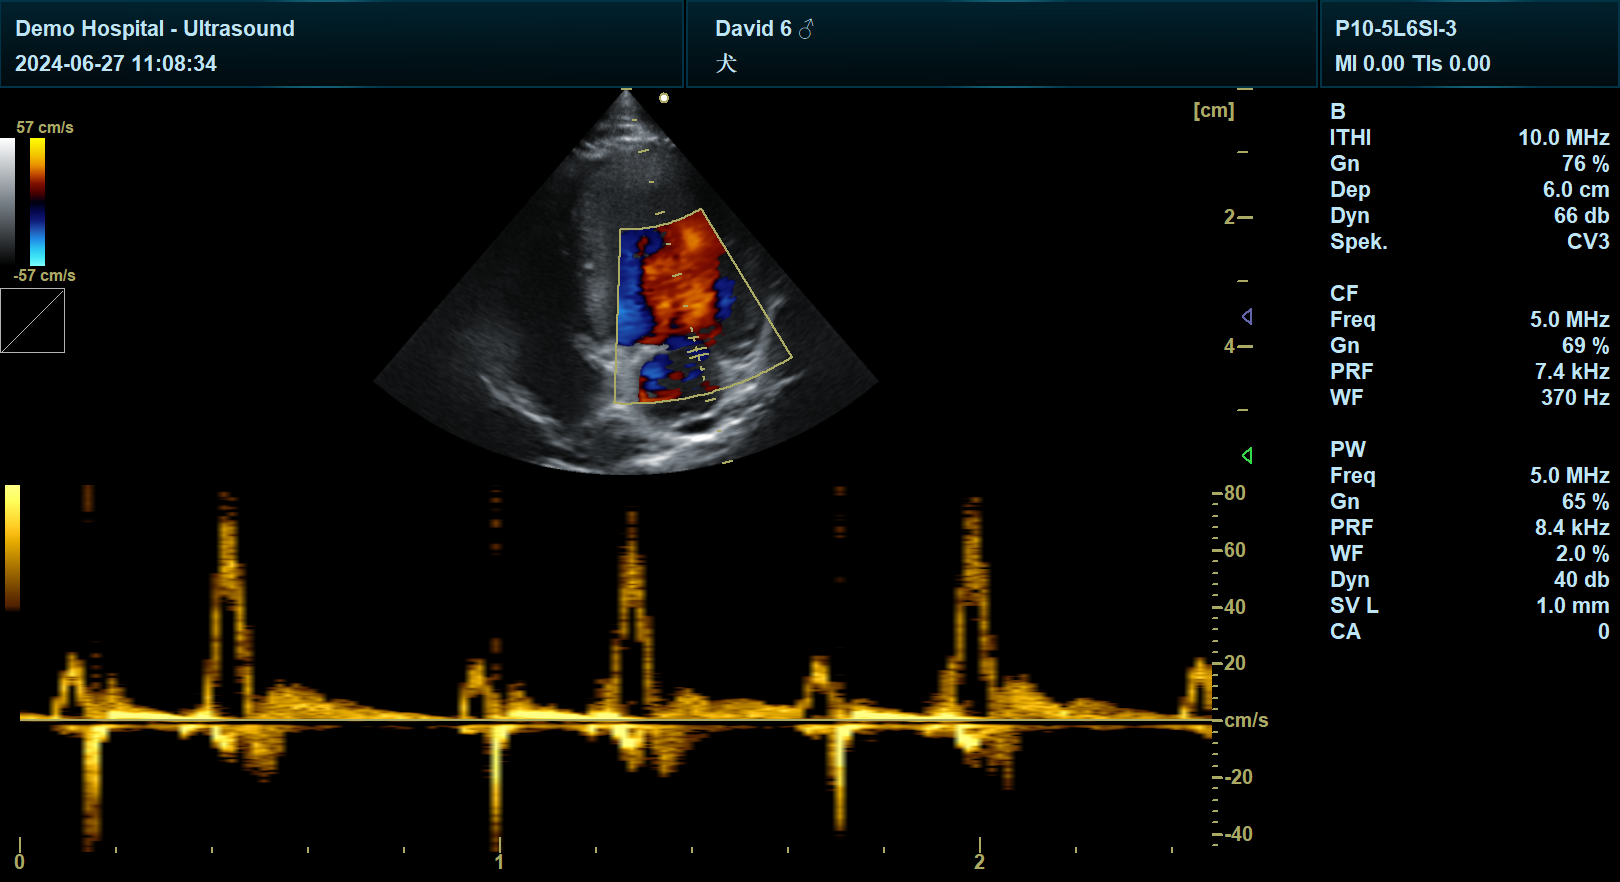

血流成像:彩色多普勒显示主动脉瓣口血流,评估是否存在反流或狭窄。

主动脉瓣狭窄:主动脉瓣增厚、开放受限,彩色多普勒显示湍流。

主动脉瓣反流:彩色多普勒显示主动脉瓣口反流束,评估反流程度。